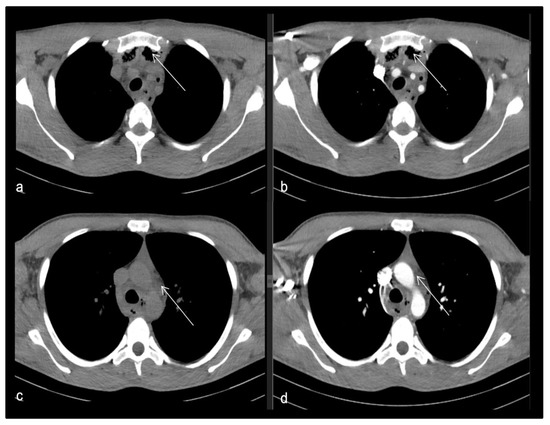

- Case 3.